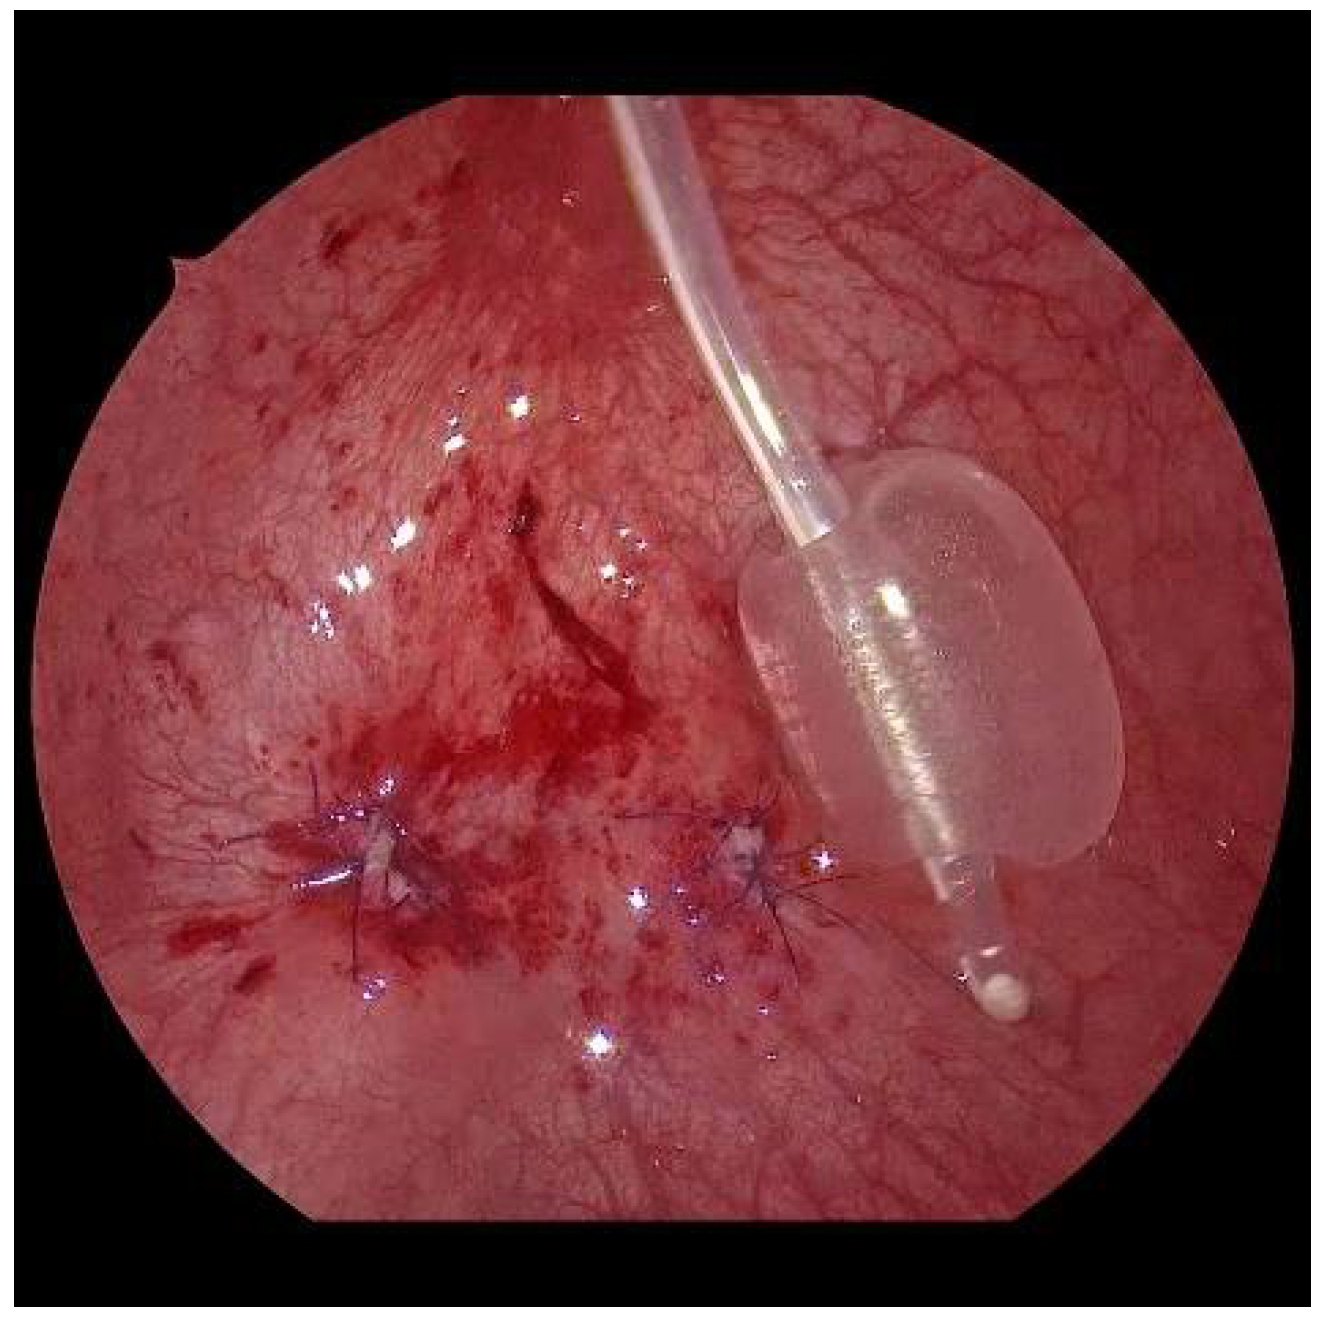

After sparingly shortening and spatulating, the neoostia are created with 5/0 polyglyconate or polyglactin sutures (Figure 7). Depending on the age of the patient, a submucosal ureteral course of 3 to 5 cm in length can thus be achieved. If the finding is unilateral, the original mucosa incision must be closed (Figure 8). Only in exceptional cases, e.g., renal insufficiency, are the ureters splinted for 6 days by percutaneously inserted splints. Finally, the bladder is drained through a balloon catheter for at least 1 to 2 days. After the trocars have been removed, the trocar incisions are only adapted cutaneously, using skin patch strips. The patients are discharged home with problem-free, spontaneous micturition, safe well-being, and regular ultrasound findings.

Figure 7.

After sparingly shortening and spatulation, the neoostium is formed on the left.

Figure 8.

Aspect at the end, with closed mucosal defect on the right and the neoostium on the left.